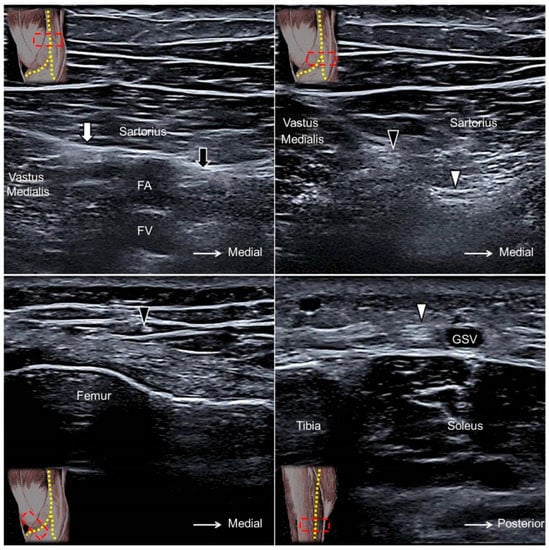

The transducer is placed in the horizontal plane at the proximal medial thigh to locate the adductor canal. The canal is bordered by the sartorius muscle superficially, the vastus medialis muscle laterally, and the adductor longus muscle deeply. The saphenous nerve can be seen as a hyperechoic oval-shaped structure inside the canal with the femoral artery and vein (Figure 13A). Moving the transducer more distally, the saphenous nerve will be seen exiting the adductor canal together with the descending genicular artery. Near the exit of the adductor canal, the saphenous nerve gives off the infrapatellar branch, emerging through the fascial plane interposed between the vastus medialis and sartorius muscles to the subcutaneous layer (Figure 13B,C, Supplementary Video S15). The sartorial branch descends and surfaces to the subcutaneous layer at the posterior aspect of the sartorius muscle. The sartorial branch courses next to the greater saphenous vein at the anterior medial aspect of the leg and ankle (Figure 13D, Supplementary Video S15) [35].

Figure 13. The saphenous nerve (black arrow) proximal to the exit of the adductor canal (A). The infrapatellar (black arrowhead) and sartorial (white arrowhead) branches of the saphenous nerve at the exit of the adductor canal (B). The infrapatellar branch on the distal femur (C) and the sartorial branch on the distal tibia (D). White arrow, nerve to the vastus medialis muscle; FA, femoral artery; FV, femoral vein; GSV, great saphenous vein.